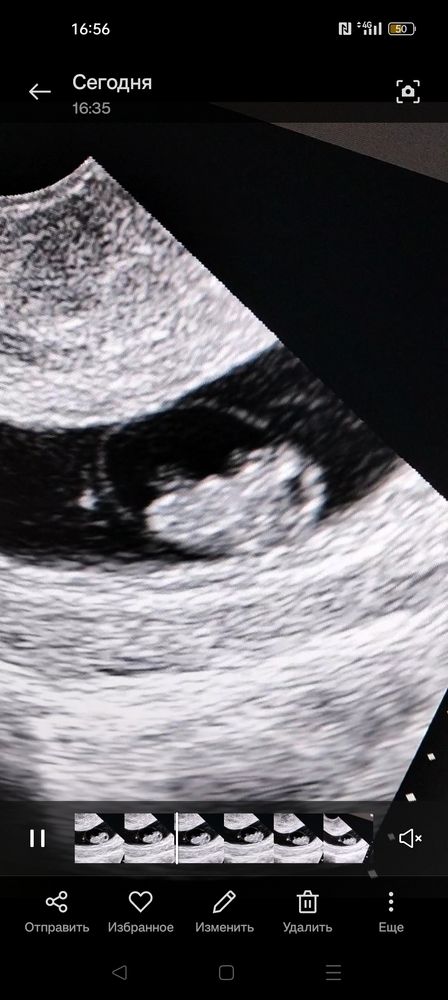

Привет! Девочки у кого было... По сроку от ПМ 8 нед, КТР 15 мм соответствует сроку, СВД 39.5 как то многовато... Чем это грозит?

Привет! Девочки у кого было... По сроку от ПМ 8 нед, КТР 15 мм соответствует сроку, СВД 39.5 как то многовато... Чем это грозит?

Такая же картина сейчас, КТр 17,7 мм, а СВД 44 мм. Читала читала я форумы и поняла, что все нормально. Ничего не значит еще. Лучше больше, чем меньше. а желточный мешочек сколько у вас?